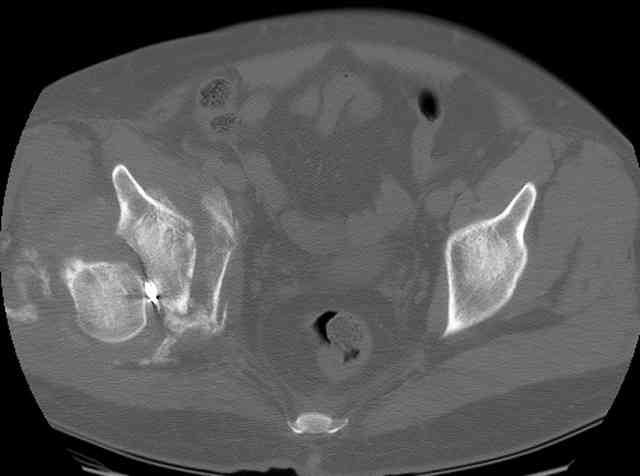

I'll include a few images of a similar injury in a similarly large male patient. This patient "showed up" in our ER c/o hip pain 2 months after being treated in the lateral position, without a quality reduction, without an anterior column transverse supporting implant, with an unbalanced plate applied too medially, with insufficient caudal segment fixation...it took over 8 hours and a 3+ l blood loss to debride the callus from front then

back, excise the HO, release his sciatic nerve, reduce the head-transverse-wall, and fix it...and now it's a staging procedure.